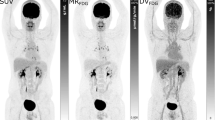

For dynamic acquisition, activity concentration changes are largest during the first minutes of acquisition (bolus transit) but depend on the rate of FDG infusion, distribution and clearance. Therefore, when partitioning list-mode data or using pre-defined time frames, one should consider a high temporal resolution for this period, especially important for pharmacokinetic analysis of two-compartment models. Improvement of temporal resolution inherently decreases the count accuracy per time frame, since the (approximate) Poisson distribution of count statistics (for prompt coincidences) dictates a relative standard deviation dependent on the inverse square root of the observed counts. As the choice of framing and the duration of FDG infusion are related, it is impossible to give general recommendations. Generally, for scanners with low sensitivity, time frame durations should be longer and consequently the rate of FDG infusion slower. The choices of different groups using dynamic acquisition for oncological purposes can be found elsewhere [48–50] (Fig. 1).

Linear regression of the plot \( {C_{PET}}(t) \cdot {C_{plasma}}{(t)^{ - 1}} \) vs \( \int_0^t {{C_{plasma}}\left( \tau \right)} d\tau \cdot {C_{plasma}}{(t)^{ - 1}} \) (“Patlak space” or “funny time”) results in slope: \( {K_i} \cdot \left( {1 - {V_b}} \right) \), from which, with an estimated Vb, MRglc can be computed. Simplification of the problem of solving differential equations by non-linear optimization to an approach amenable to linear regression avoids many problems inherent in the former approach: sensitivity to noise in the time-activity concentration curves, parameter covariance, local minima in the approximate solution to the differential equations and dependence of parameter estimates on starting guesses. As a trade-off only the Ki, but not the individual kinetic parameters, is estimated. An example is provided in Fig. 3.

Hoekstra et al. reviewed [99] and compared [83] 34 variations of previously mentioned methods to obtain glucose consumption (2 T/N, 12 SUV, 2 Sadato, 2 SKM, 5 Patlak, 10 TLE and one “2 ROI, 6P” variations) on 30 randomly selected dynamic FDG PET scans in 19 lung cancer patients. Since incorporation of k4 did not improve fits, the Sokoloff 3K model was used as gold standard. The reliability of the gold standard was considered high since the test-retest variability (ICC = 0.95) and intra- and interobserver variability (ICC = 0.98 for both) were small. Of the 34 models tested, 10 met the required minimal correlation with the gold standard (R 2 > 0.95). They concluded that the best simplified options are SUVBSA+glucose (40–60 min or 50–60 min post-injection), Sadato method based on BSA and Patlak graphical analysis (10–60 min post-injection). Similarly, Lammertsma et al. [100] pooled the results of three studies comparing methodological aspects of response monitoring in lung [83], breast [101] and gastro-oesophageal [102] cancer (in total 170 FDG PET studies) and show excellent correlation with the Sokoloff 3K model of Patlak MRglc (ICC = 0.98), SKM (ICC = 0.94), SUVBSA+glucose (ICC = 0.91) and SUVBSA (ICC = 0.91). They conclude that although Patlak MRglc has the best correlation with the gold standard, it remains to be proved that these findings are of clinical relevance. Changes found by SUV estimation may still represent a relevant response [103, 104].